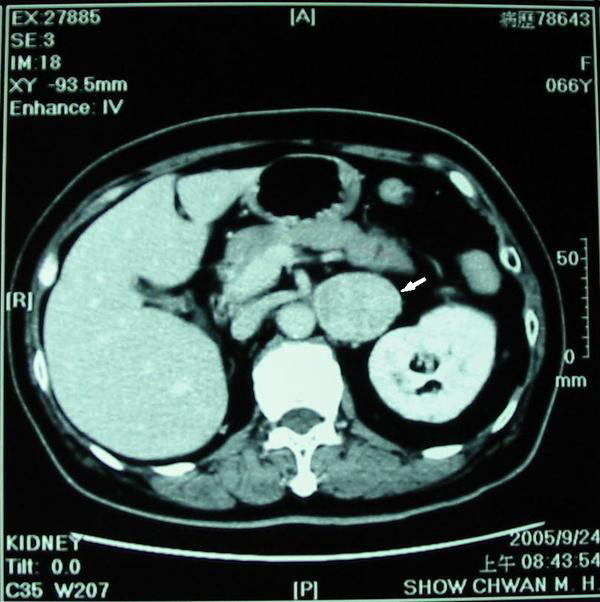

A 3.6x 3.7cm retroperitoneal mass was found incidentally by renal ultrasonography (Fig. 1). CT scan showed an enhanced tumor 4.5x3.5x4.0cm in size (Fig. 2). The tumor was located in the left suprarenal space indicating an adrenal tumor. 64-slice CT revealed that the tumor mass was just between the renal artery and the renal vein (Figs. 3A, 3B). Preoperative CT-guided biopsy revealed pheochromocytoma. Urine catecholamine was 3.44 mg/24 hr (normal 1.0-7.5mg/24hr) and plasma renin was 3.03mol/L (normal 0.5-5.7mol/L).

Computed tomogram showing a large and enlarged tumor mass (arrow) about 4.5x3.5x4.0 cm in size. The tumor was located at left suprarenal space indicating an adrenal tumor.